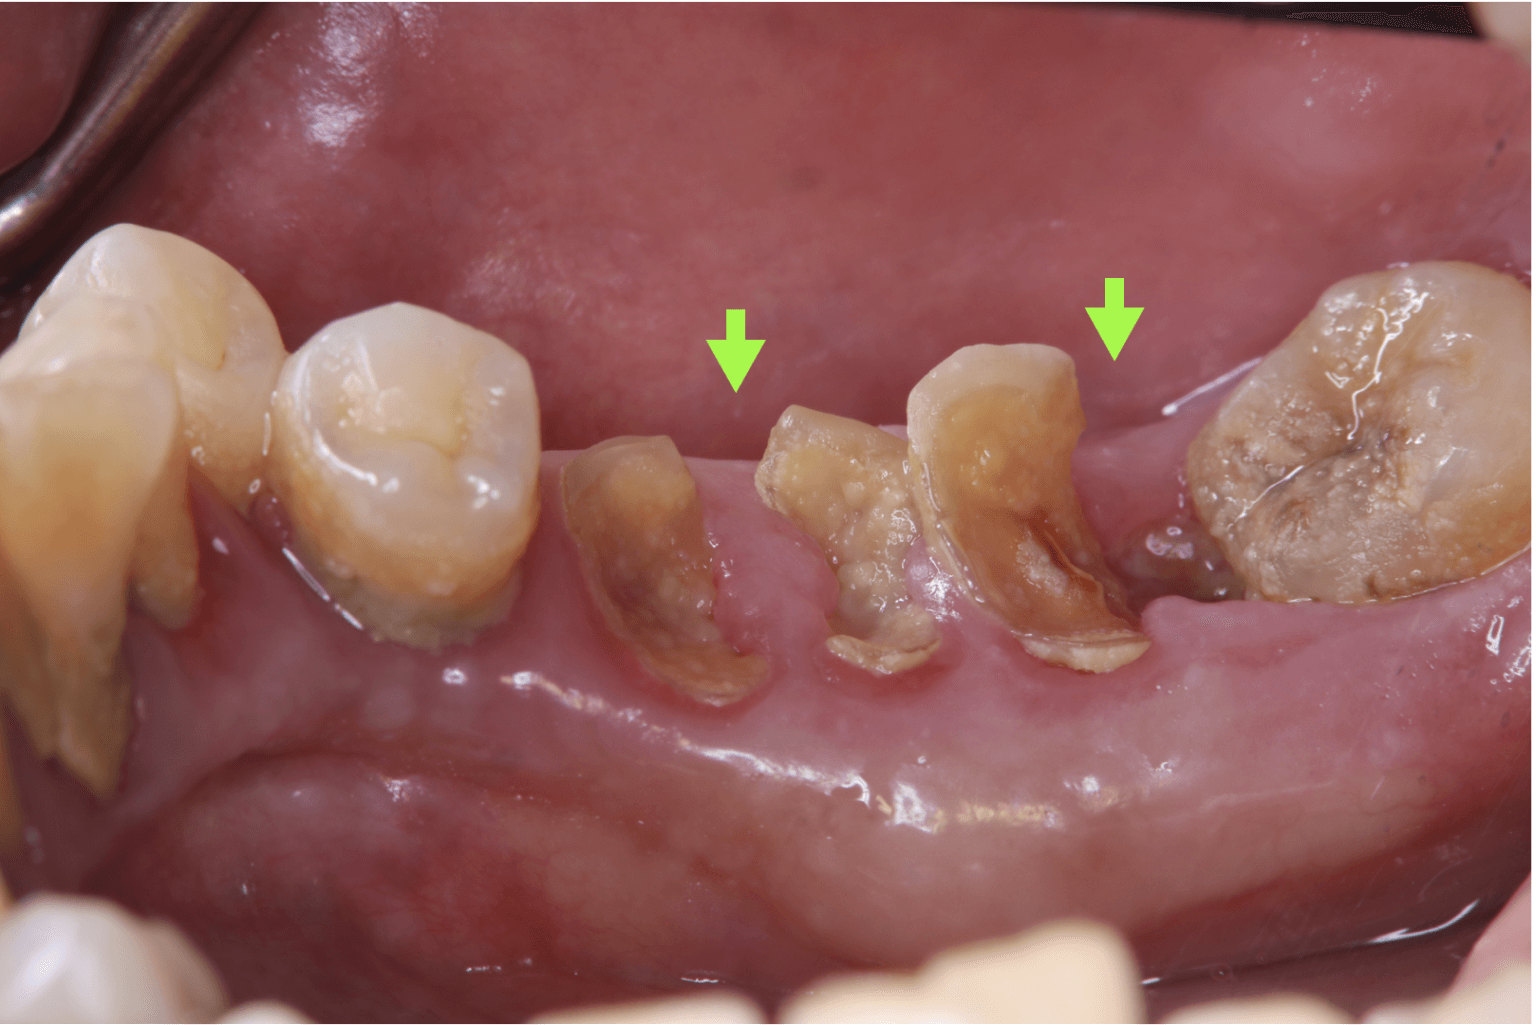

虫歯: 虫歯が進行すると、歯が崩壊し、食べ物の残りかすが溜まりやすくなり、細菌の活動が活発になるため、口臭の原因となります。進行した虫歯は特に強い口臭の原因となります。